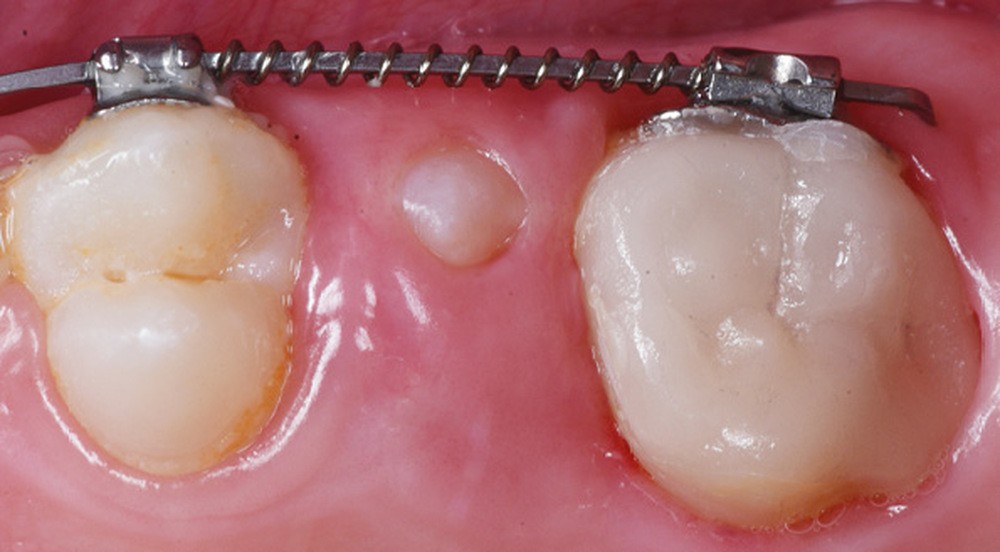

Kara (10 ans) se présente en consultation pour une sensibilité accrue au niveau de 26. L’examen clinique y révèle la présence d’une restauration de grande étendue ainsi qu’une fracture amélaire avec perte de l’hémi-cuspide mésio-vestibulaire. Cette dernière est touchée par la présence d’un défaut de structure coloré (fig. 1). Après examen des premières molaires, le diagnostic d’hypominéralisation molaire-incisive (MIH) est posé.

Le protocole de préparation de la dent ainsi que celui concernant l’assemblage de l’overlay céramique (fig. 2 à 7) suivent une séquence clinique habituelle [7, 8], à l’exception de deux étapes. Nous proposons ici, à la suite de l’éviction carieuse, d’intensifier la désinfection par l’utilisation d’O3 (fig. 3). Aussi, il nous paraissait intéressant, une fois la préparation prothétique effectuée, d’infiltrer cet « émail MIH » afin de potentialiser le collage et renforcer ses propriétés mécaniques ; l’infiltration résineuse agirait à l’échelle de l’émail comme le scellement dentinaire immédiat agit à l’échelle de la dentine (fig. 5). Une désinfection optimisée, un bandeau d’émail renforcé et le choix d’une restauration minimalement invasive qu’est l’overlay conduisent à un pronostic plus favorable pour l’avenir de cette dent, d’ailleurs incluse par la suite dans un traitement orthodontique (fig. 8).